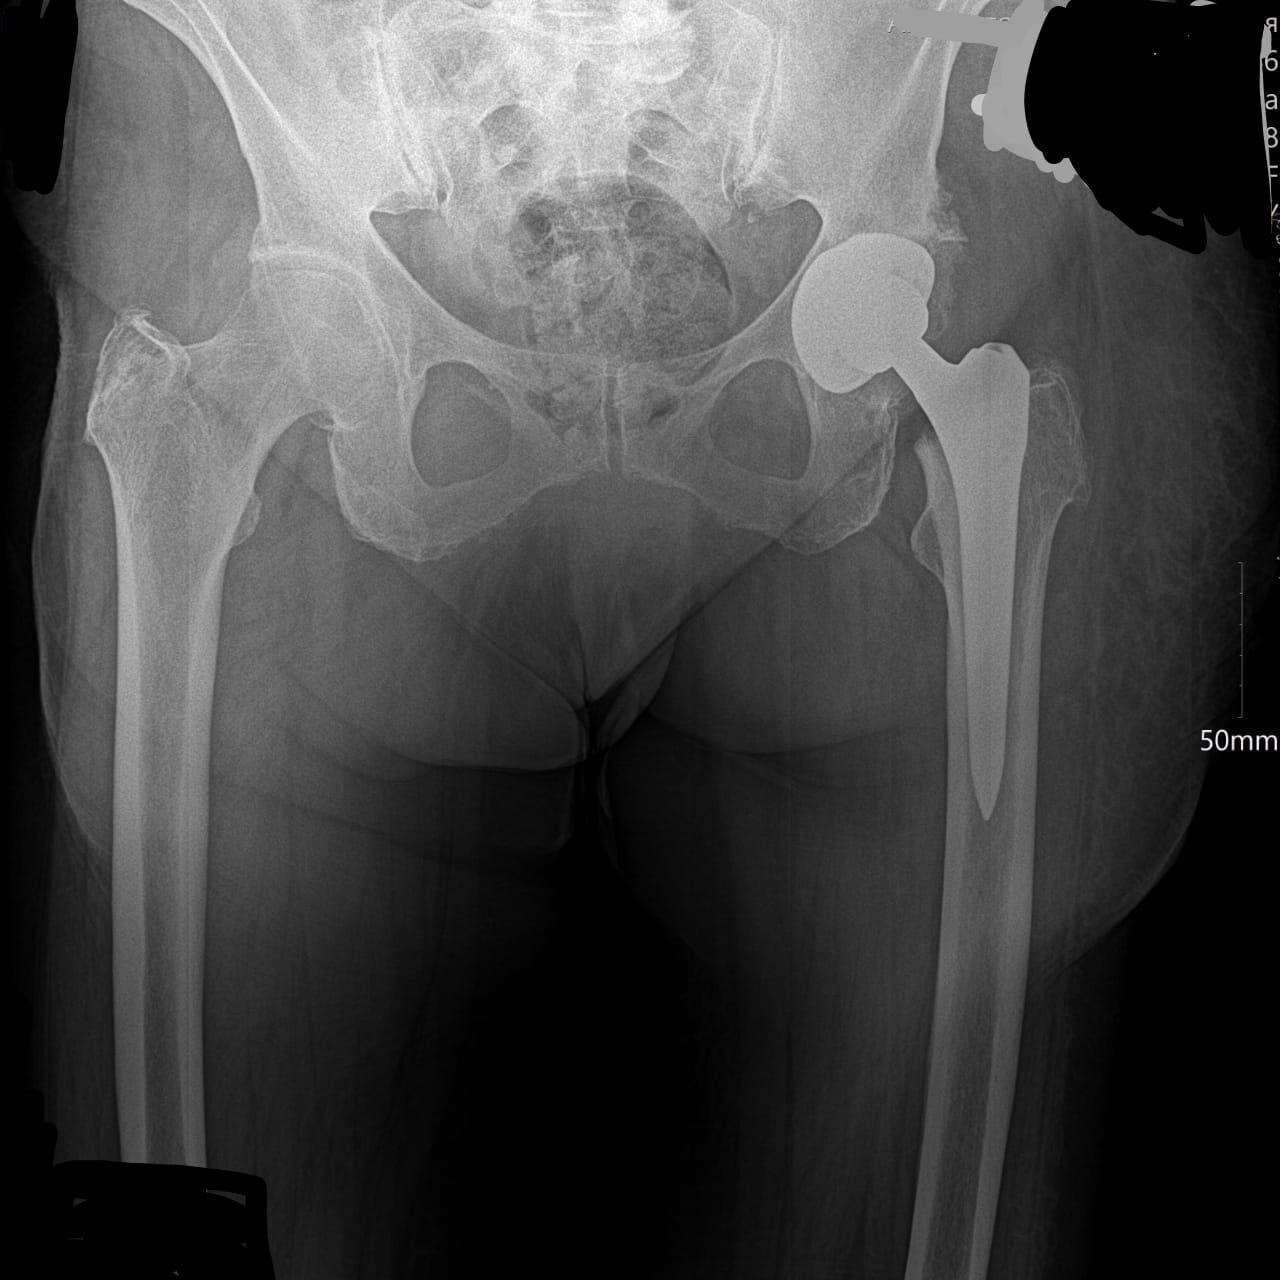

Рентгеновский эффект создает фантастические композиции в этих фотографиях девушки, чье тело становится прозрачным, демонстрируя скелет и внутренние органы. Она позирует в разных позах, ее силуэт светится загадочным свечением. Каждый кадр передает атмосферу научной фантастики и медицинского искусства. Ее кожа кажется полупрозрачной, позволяя увидеть кости и мышцы. Фотографии рассказывают о хрупкости человеческого тела и его внутренней красоте. Девушка то стоит в задумчивости, то делает грациозное движение. Эти иллюстрации вдохновляют на размышления о человеческой анатомии и уязвимости. Каждая картинка - это момент прозрения, когда внешнее уступает место внутреннему. Девушка воплощает образ современной Медузы, сочетающей красоту и загадочность.

Сквозь материю: тайны анатомии